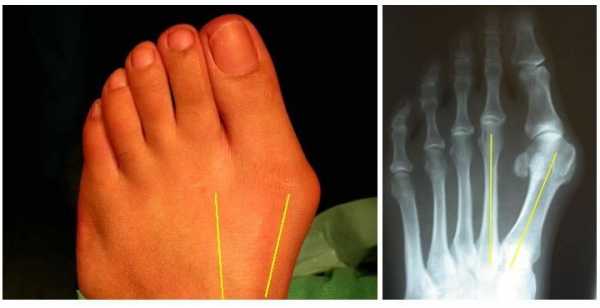

Суть патологии

Вальгусная деформация стопы — патологическое искривление сустава большого пальца внутрь стопы и выход наружу первой плюсневой кости. Из-за этого страдают все остальные костные элементы, связки и сухожилия, поскольку неправильно распределяется нагрузка на ногу.

вальгусная стопа

вальгусная деформация стопы